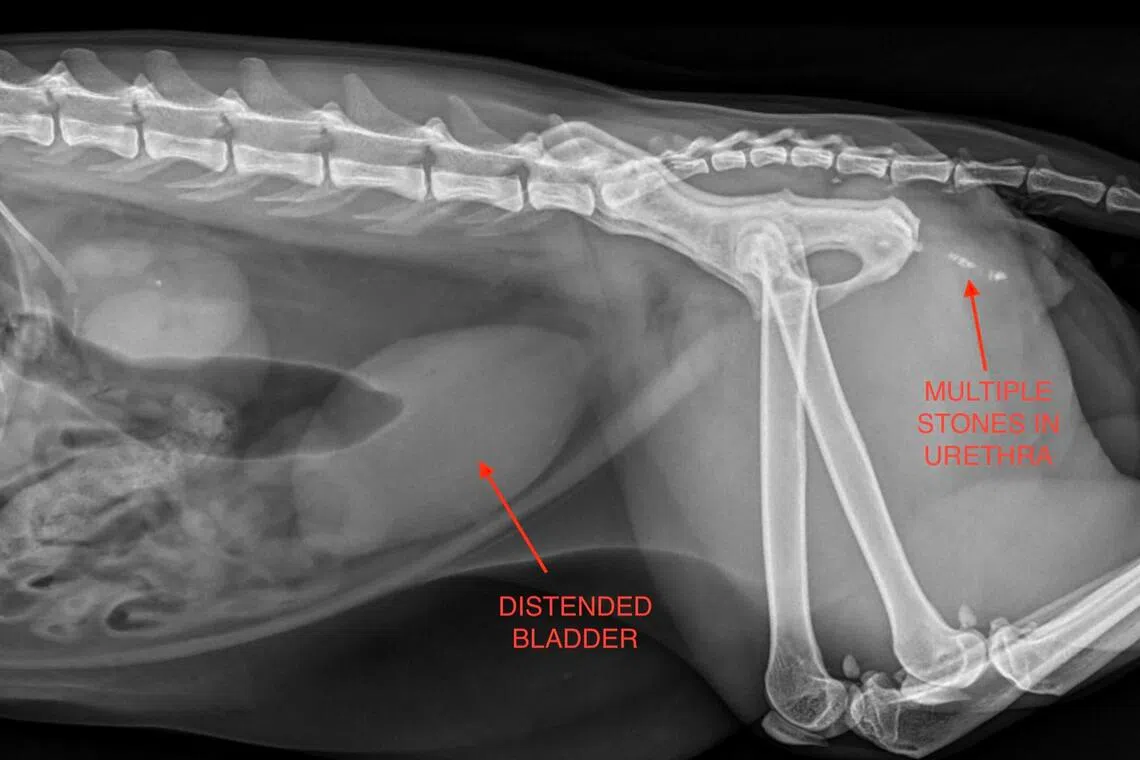

Stones lodged within the urethra causing urinary blockage.

PHOTO: WESTSIDE VETERINARY EMERGENCY AND REFERRAL HOSPITAL